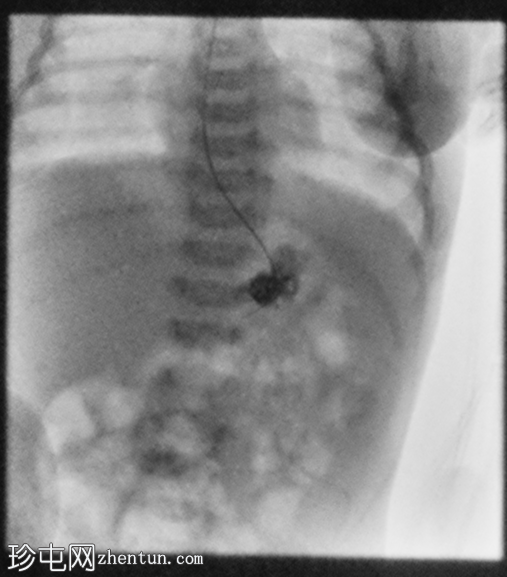

X线片

正位

胃部初始显影,并立即反流至食管裂孔疝。在其近端可见管径正常的远端食管。十二指肠降部和横部显影较弱,左上腹可见数段管径较小/部分减压的近端小肠显影。